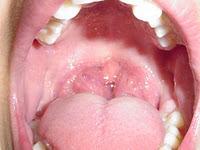

- La frecuencia de los episodios de anginas es de al menos siete episodios en el último año, al menos 5 episodios por año durante 2 años o al menos 3 episodios por año durante 3 años. Estos episodios han de ser anginas “verdaderas”: dolor de garganta, temperatura> 38,3 ° C, adenopatías cervicales (ganglios) y exudado amigdalar (pus) o un test positivo para estreptococo del grupo A beta-hemolítico

- El niño tiene infecciones repetidas con amígdalas hipertróficas que pueden afectar a su sueño, su crecimiento o a su rendimiento escolar. Otra indicación es la hipertrofia amigdalar, sin infecciones, que interfiere el sueño tranquilo (ronquidos, apneas, cambios de posición frecuentes) que se puede demostrar con un estudio del sueño (polisomnografía) si es necesario